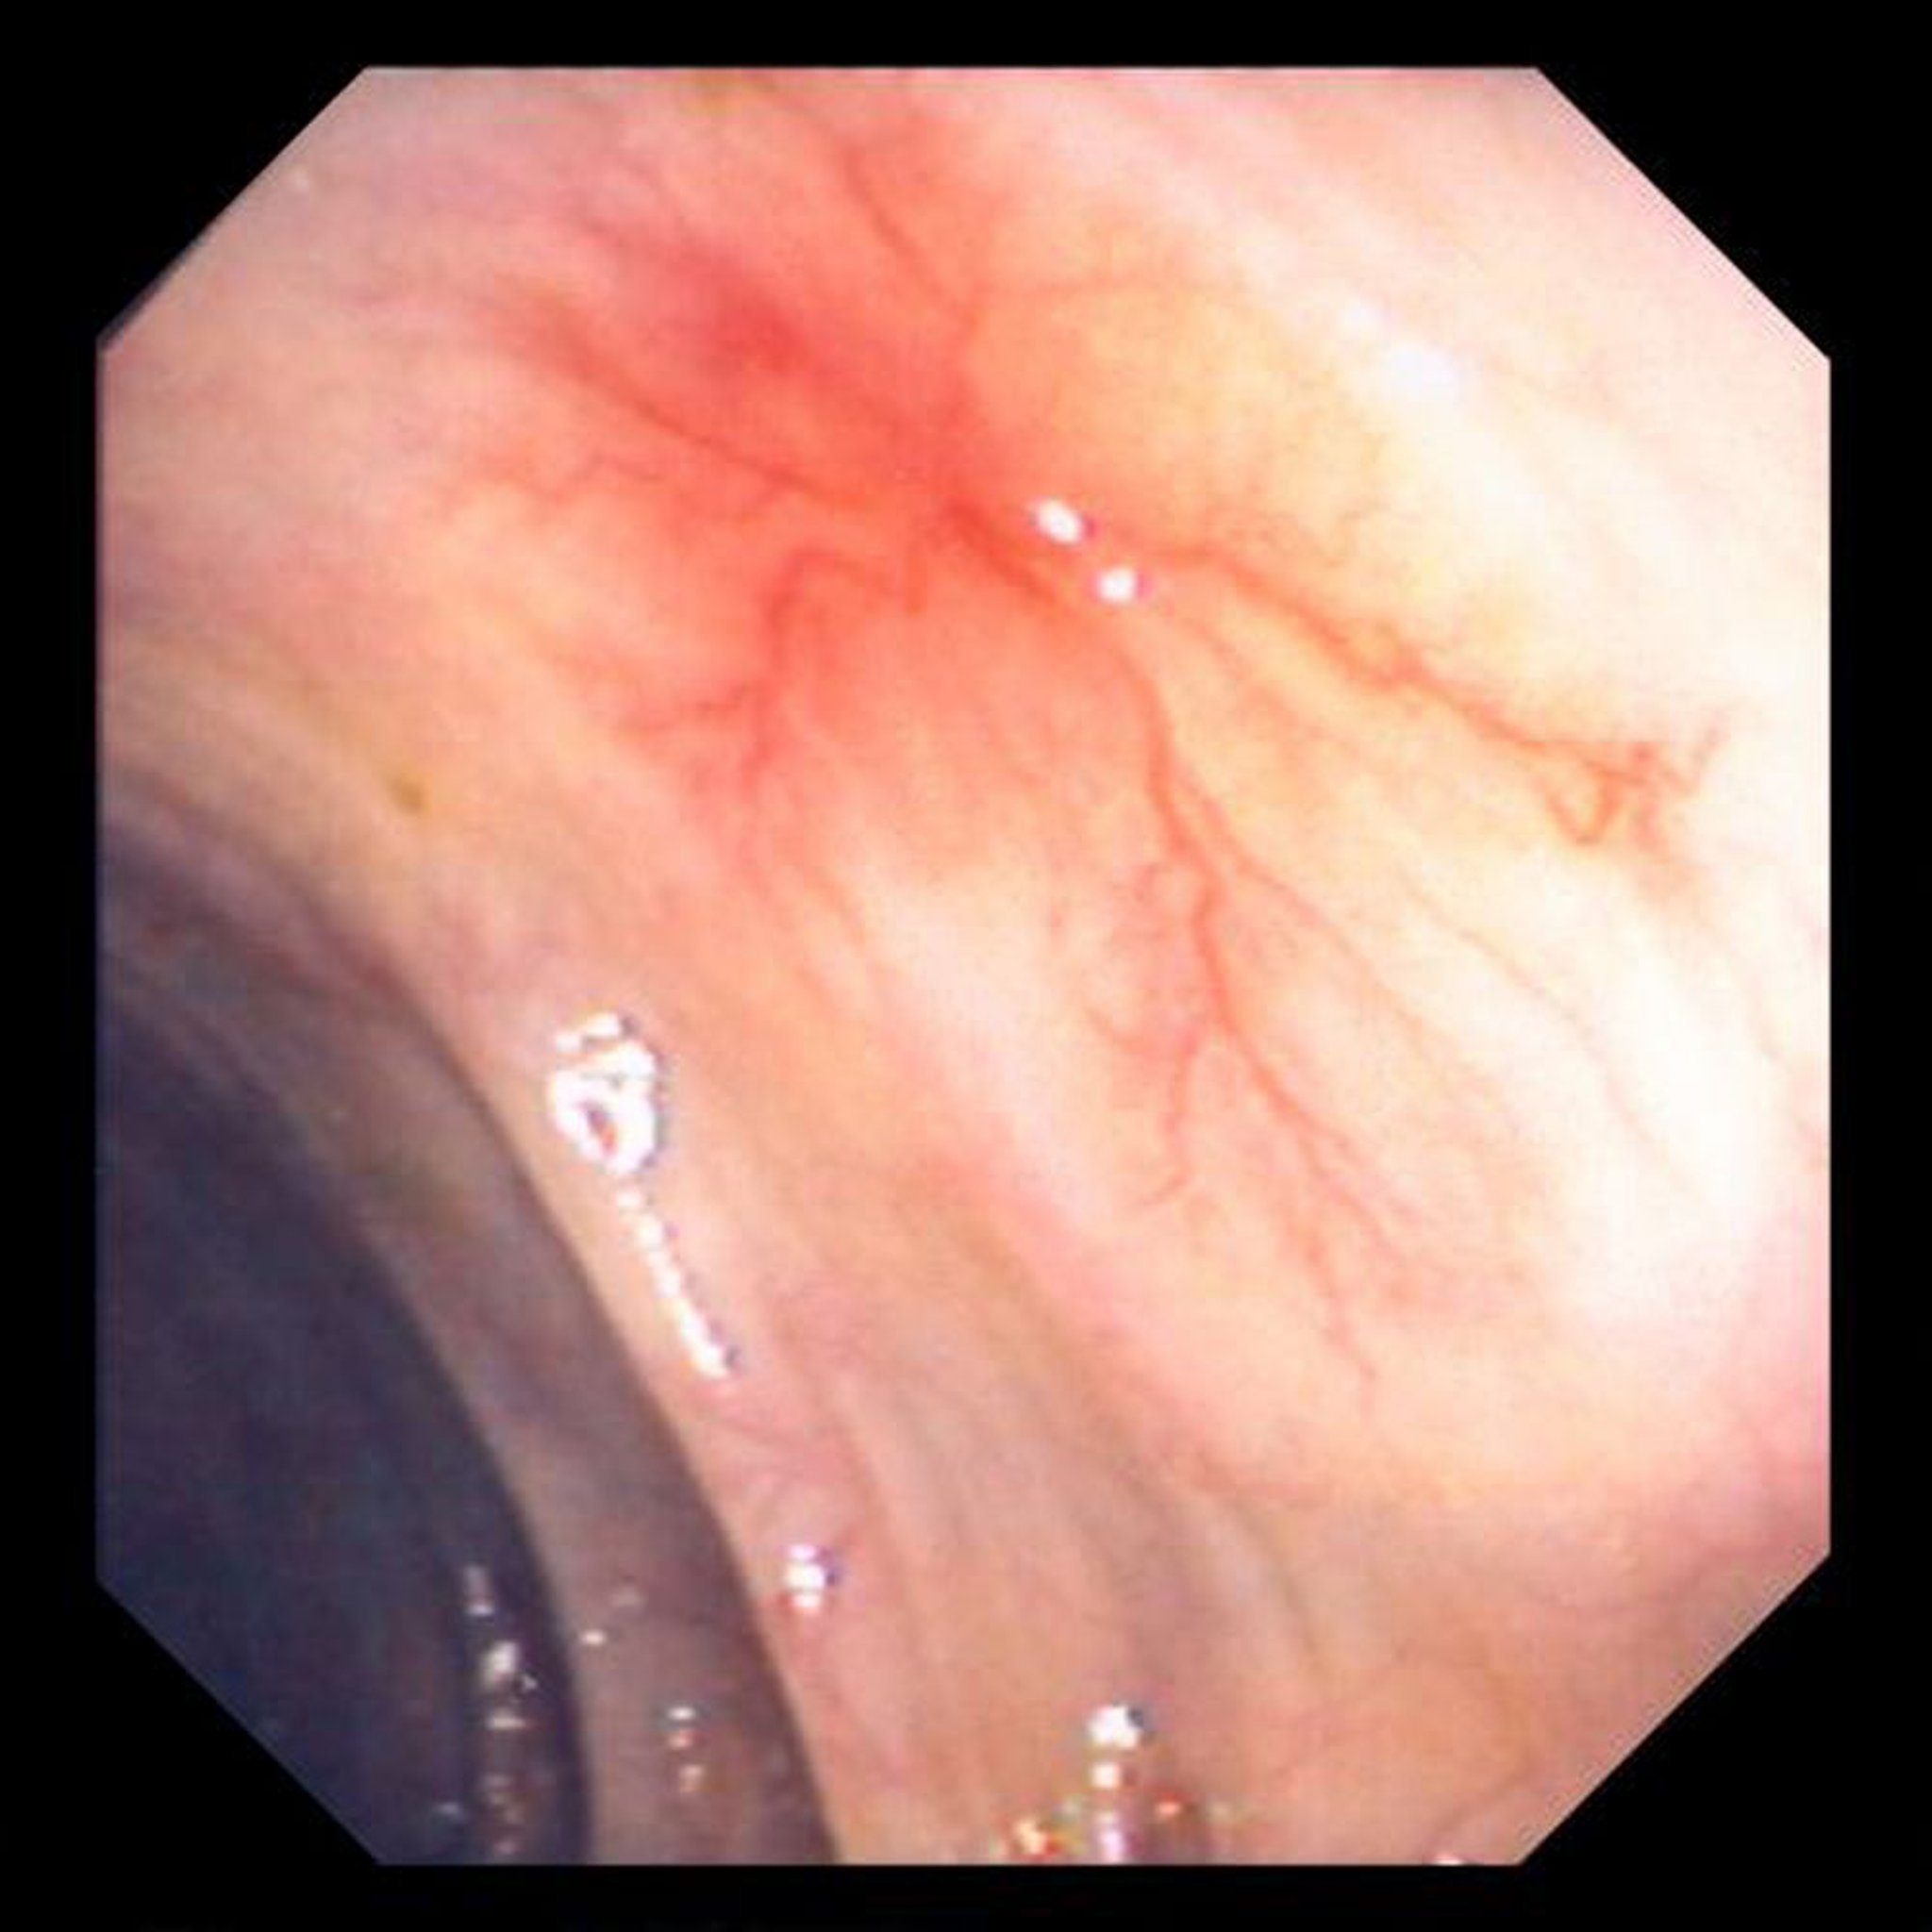

Angiodysplasie

Cette photo montre une ectasie vasculaire de la paroi intestinale.

Image provided by David M. Martin, MD.